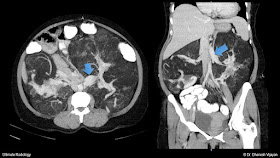

CT Abdomen was requested for further evaluation of the abdominal pain. In the plain CT sections, the aorta was seen dilated, with proximal abdominal aorta measuring up to ~3.5cm in outer diameter. Highest section of the scan did show the dilated distal descending thoracic aorta with hyperdense peripheral crescent, indicating acute intramural hematoma (/thrombosed false lumen of dissection), which necessitates the scan to be taken from arch vessels to iliac arteries, to assess the involvement of ascending aorta, arch and to look for the inferior extent.

| Dilated proximal abdominal aorta, raising the suspicion of dissection in a 40yr old female patient. |

| Hyperdense crescent indicating acute intramural hematoma. |

Above image shows the proximal end of the intramural hematoma, beginning just distal to the left subclavian artery origin, making it a Stanford type B dissection. Ascending aorta and arch branches were not affected (not shown).

The hyperdense hematoma can be seen slightly rotating / whirling in an anticlockwise fashion, to come towards the left lateral aspect of aorta (see below), from the posteromedial aspect.